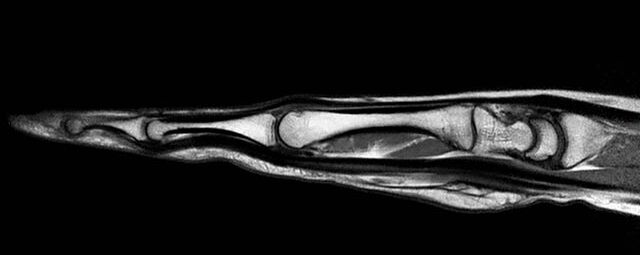

Gelenke

• Beurteilung von Knochen, Bändern und anderen Weichteilstrukturen der Gelenke nach Unfall.

• Arthrosediagnostik (Knorpelschaden)

• Impingement-Symptomatik

• Ursachenklärung bei wiederholter spontaner Gelenkluxation

• Ausbreitungsdiagnostik bei Gelenkentzündung, z.B. im Rahmen von rheumatischen Grunderkrankungen